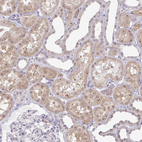

Immunohistochemical staining of human colon, kidney, liver and testis using Anti-RSL24D1 antibody HPA062724 (A) shows similar protein distribution across tissues to independent antibody HPA063392 (B).